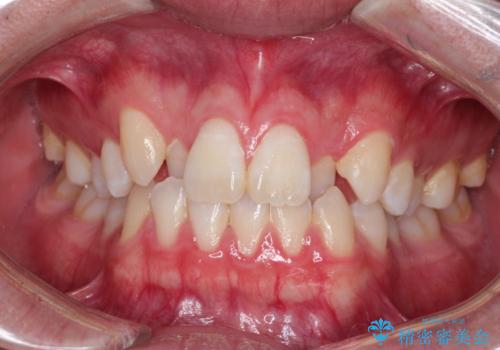

[前歯のねじれ 部分]ワイヤーとマウスピースの併用矯正治療

担当医 大元洋佑